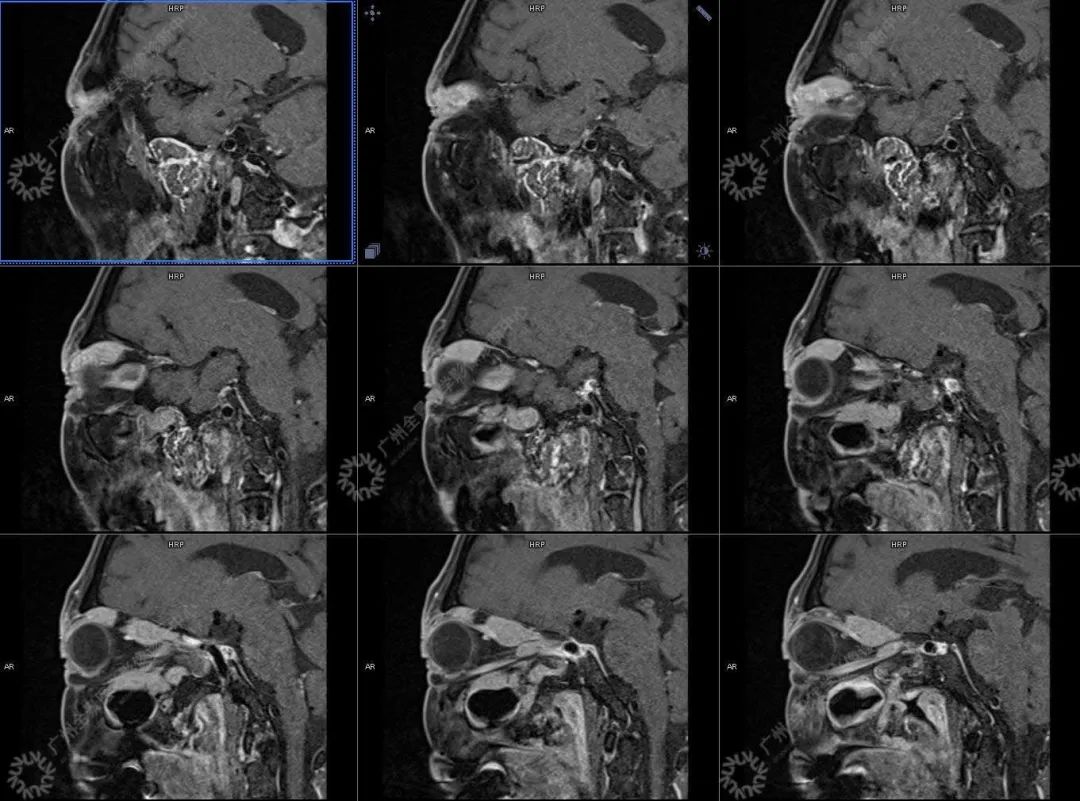

患者:男性, 71 岁

主诉:视力下降 2 年

现病史:双眼部隐痛、流泪,视力下降 2 年

结合影像及实验室检查,临床最终考虑 IgG4 相关性疾病。